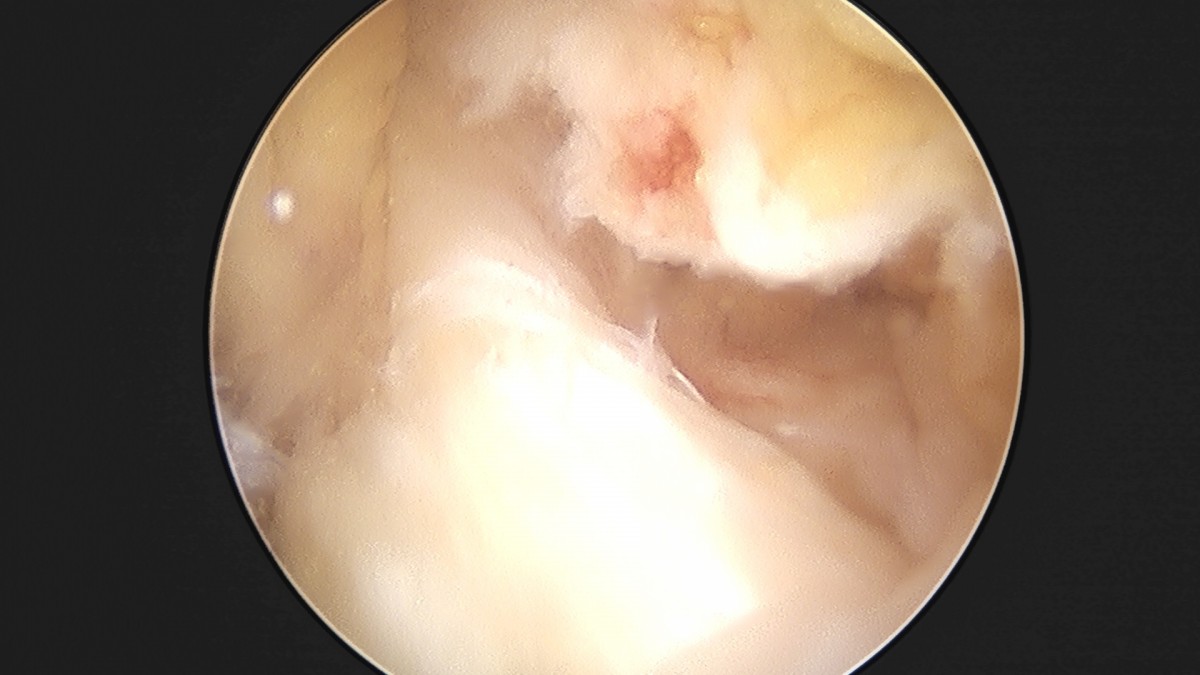

이재상원장님 무릎 반월상 연골판 절제술 조미O 환자

작성자 최고관리자 댓글 0건 조회 368회 작성일 25-09-16 16:01